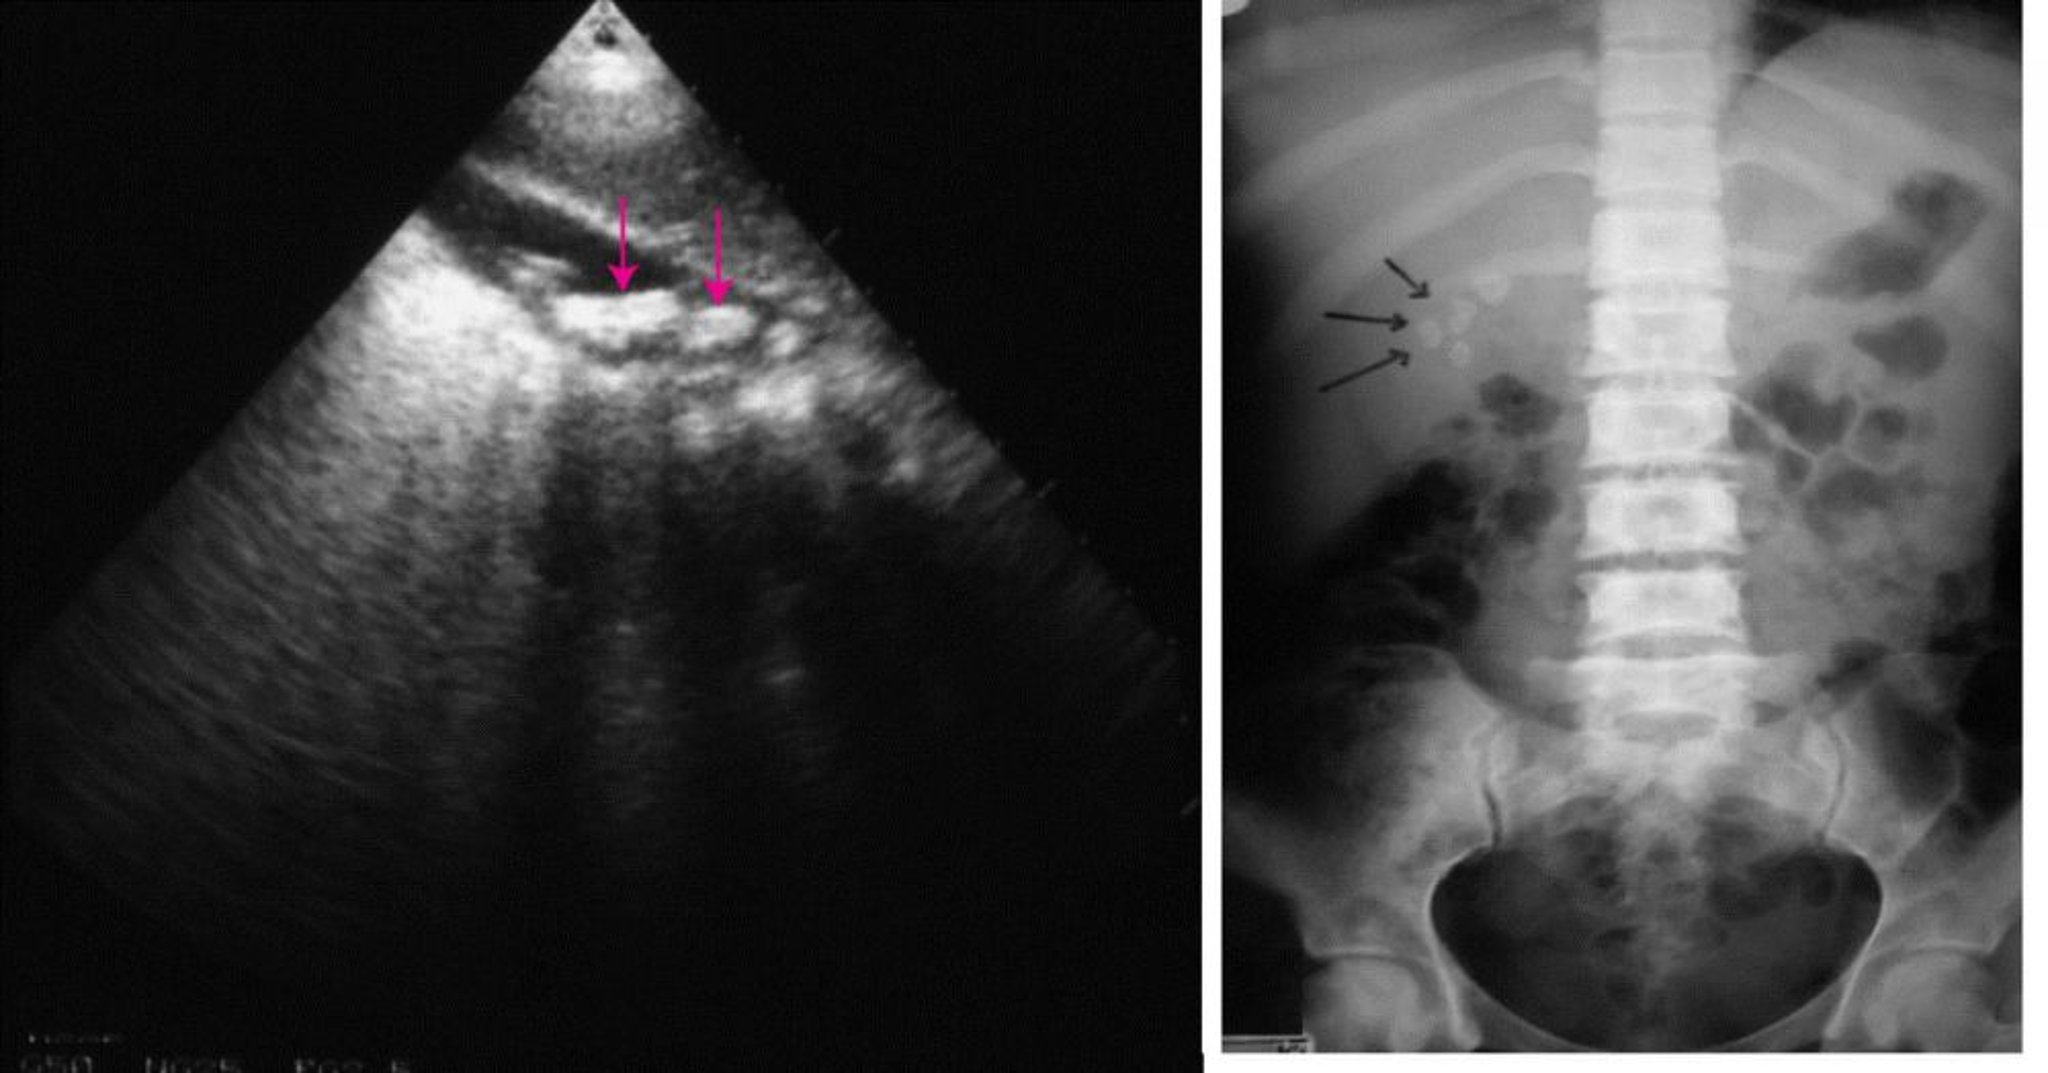

On the left, an abdominal ultrasound showing multiple gallstones (arrows). On the right, a plain abdominal radiograph showing radiopaque gallstones (arrows).